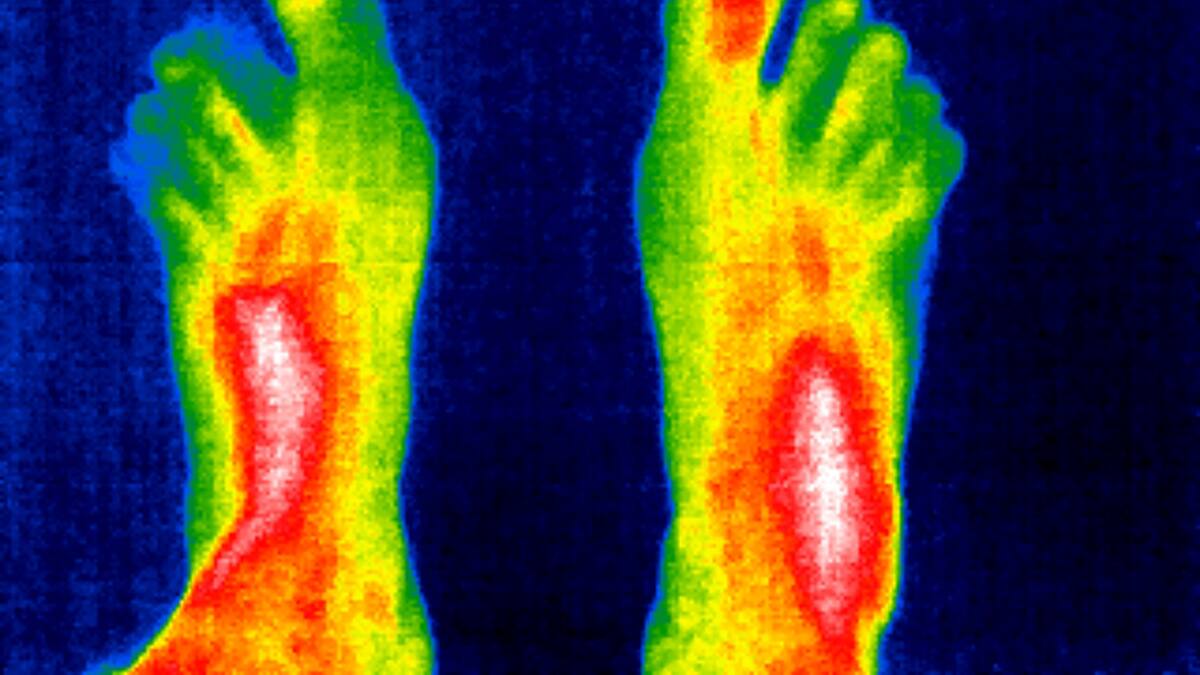

¿Frioleros o calurosos? El termómetro interno que nos mantiene con vida

Una investigación internacional liderada por el español Félix Viana, del CSIC, recibe un millón y medio de dólares para estudiar los receptores moleculares del frío y el calor